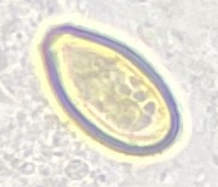

Schistosoma haematobium ovum

Clonorchis sinensis ova

Clonorchis sinensis ova